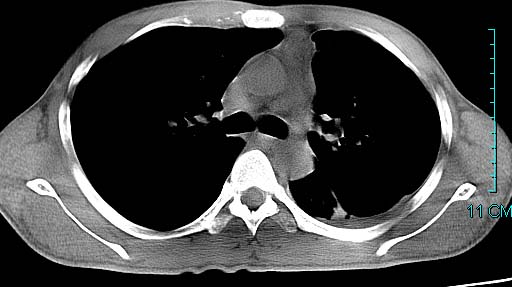

以下是引用ctkz987在2006-3-28 13:04:00的发言:[br]左侧胸腔积液穿刺后多发气液平(多房性),结合临床有高热不除外合并感染。

以下是引用qian在2006-3-28 14:32:00的发言:[br]左肺下叶大片状阴影,密度不均,见有条片影和空洞及气液平,少量胸腔积液伴有胸膜增厚,从图像看积液密度比水的密度高,结合病史,考虑左下肺化脓性炎症伴有脓胸。

以下是引用wawaquan在2006-3-28 22:25:00的发言:[br]左上肺舌段多发斑片影。结合“男24y咳嗽咳痰气促伴高热(38.5--39.5)20多天”及穿刺史,[br]考虑1 左下肺化脓性炎症;2脓胸。

以下是引用乡医在2006-3-28 18:37:00的发言:[br]左侧多发液气平面结合患者男24y咳嗽咳痰气促伴高热(38.5--39.5)20多天,查胸水:ldh239.3,总蛋白59.19,tb-ab阴性,利凡它试验+,红c2.7*109,白c1.08*109,分类淋巴92%分叶8%,考虑1脓胸2肺隔离征感染